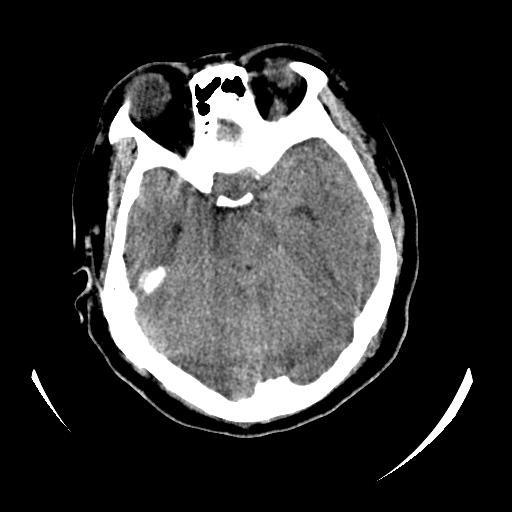

女,53岁,发现昏迷1天,血压不高,有精神病史。临床诊断:脑梗死?

ct诊断:1、双侧基底节区对称性脑梗塞。

2、双侧额叶、枕叶广泛密度减低,考虑缺血梗塞可能性大。

3、脑池小,脑沟浅,提示颅内高压。

测左枕叶白质ct值 约22hu 。请各位老师给出恬当诊断。

征象:病变呈对称性分布于双侧大脑半球,累及范围广泛,白质较灰质密度减低更为明显;脑沟变浅,脑池变窄;

双侧环池,四叠体池显示模糊,原因?建议增强